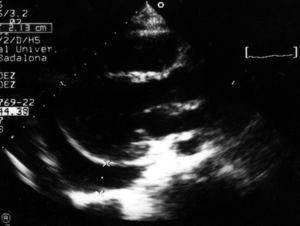

Se presenta el caso de un paciente de 12 años, intervenido quirúrgicamente de una comunicación interauricular tipo seno venoso sin incidencias, que acude 2 meses más tarde a urgencias por fiebre, y dolor torácico de características pericardíticas, con una analítica sanguínea que muestra leucocitosis, desviación a la izquierda, y aumento de la proteína C reactiva. Se le practica un electrocardiograma y un ecocardiograma que confirman el diagnóstico de pericarditis aguda (fig. 1). Se descarta etiología infecciosa y autoinmune, y con el antecedente de la cirugía cardíaca previa se sospecha un síndrome pospericardiotomía. Se inicia tratamiento con AINE, con buena respuesta, siendo suspendidos 2 meses más tarde.

Figura 1. Ecocardiografía 2D. Eje paraesternal largo mostrando una gran acumulación de líquido pericárdico, de predominio en cara posterior.